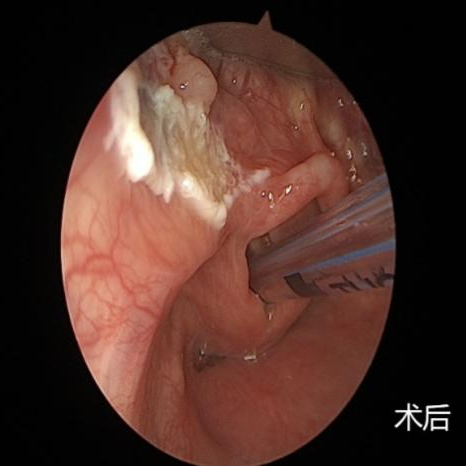

眼前的这个新生儿,3.46公斤、会厌囊肿、困难气道、纤支镜引导清醒插管……每一项单拿出来对麻醉医生都是不小的考验,何况是这几项叠加在一起,难度和风险成倍增加,稍有不慎,就有可能危及患儿生命。好在麻醉手术部有一支专业的医护团队,最终在医护人员的密切配合下,通过纤支镜引导,成功为患儿插入气管导管,随后耳鼻喉科医生也顺利切除了这颗“定时炸弹”。

图片可能引起不适,请谨慎观看